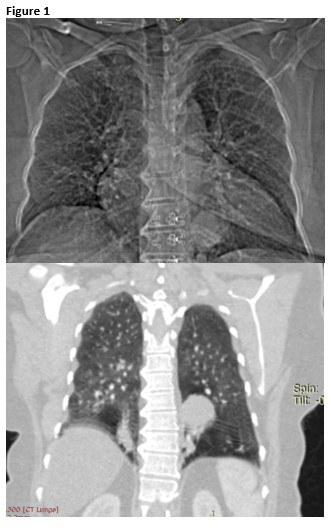

Routine labs were within normal limits. Her chest film and chest CT scan with IV contrast are shown below (Figure 1).